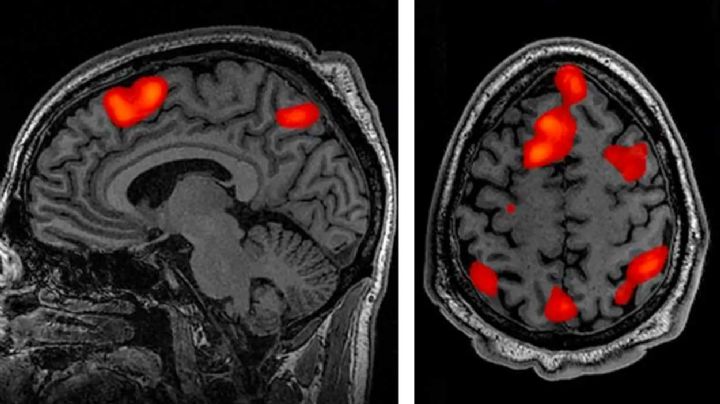

Resonancia Schumann: Cómo la Tierra afecta al cerebro y la conciencia

11/3/2026 | Científicos exploran la profunda conexión entre las pulsaciones electromagnéticas del planeta y los procesos cognitivos humanos